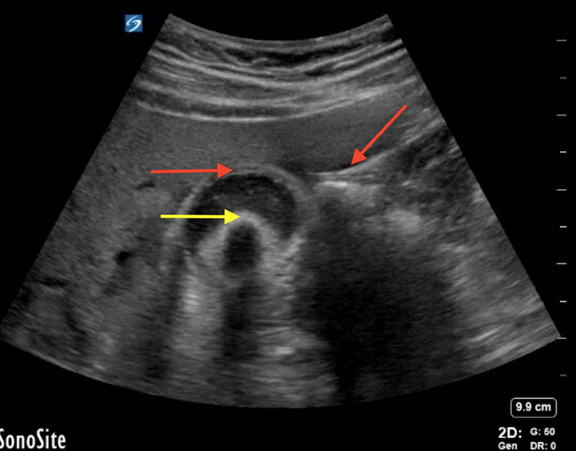

Figure 2. Cholecystitis |

Cholecystitis evidenced by gallstone (yellow arrow) wall thickening with pericholecystic fluid (red arrows). Sludge also is present inside the gallbladder. |

Image courtesy of Daniel Migliaccio, MD, FPD, FAAEM. |